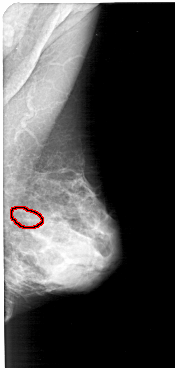

A_1570_1.RIGHT_CC

RIGHT_MLO LINES 5146 PIXELS_PER_LINE 2446 BITS_PER_PIXEL 12 RESOLUTION 43.5 OVERLAY

FILE: A_1570_1.RIGHT_MLO.OVERLAY

TOTAL_ABNORMALITIES 1

ABNORMALITY 1

LESION_TYPE CALCIFICATION TYPE PLEOMORPHIC DISTRIBUTION CLUSTERED

ASSESSMENT 4

SUBTLETY 1

PATHOLOGY MALIGNANT

TOTAL_OUTLINES 1